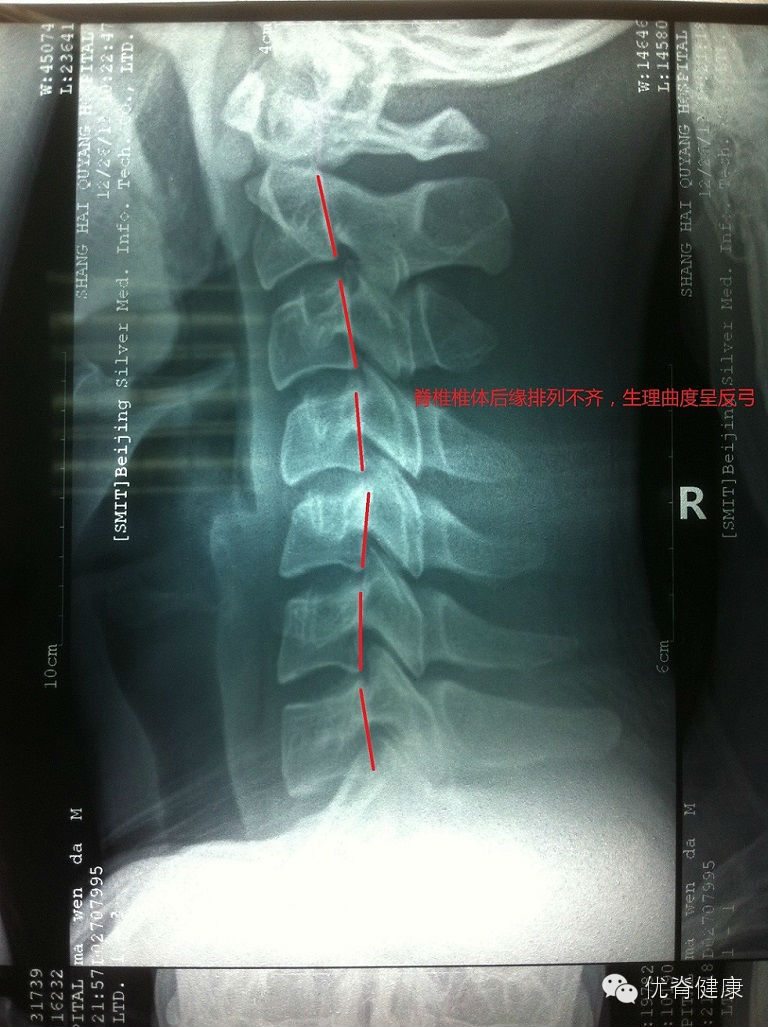

环枢关节错位,颈椎生理曲度反弓,轻度右侧弯,部分骨质增生;腰椎轻度左侧弯,伴骶椎S1隐裂;颈腰部肌群不同程度劳损,以上颈部及下腰部肌群劳损较为明显。

评估分析:颈椎软组织劳损,伴环枢关节错位,颈椎生理曲度反弓,伴轻度右侧弯。腰椎轻度左侧弯,腰肌劳损。